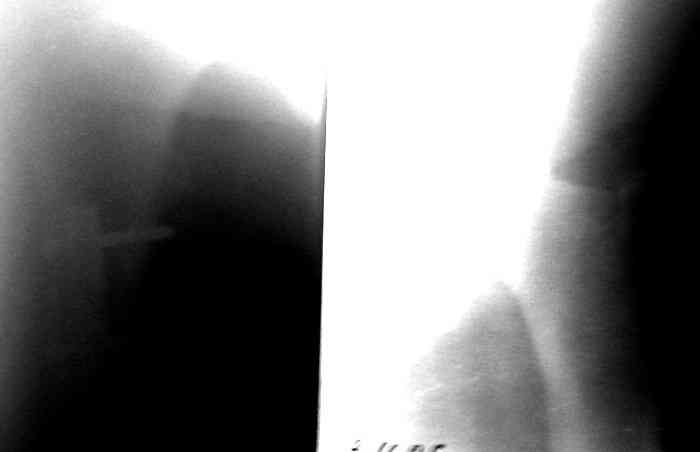

Рг в приложении.

КАН> допущенные ошибки. Спасибо. Рг в приложении.

Снимки вполне симпатичные. Единственное, по ротации не понял, уж больно неразборчивый тот, который без гвоздя.